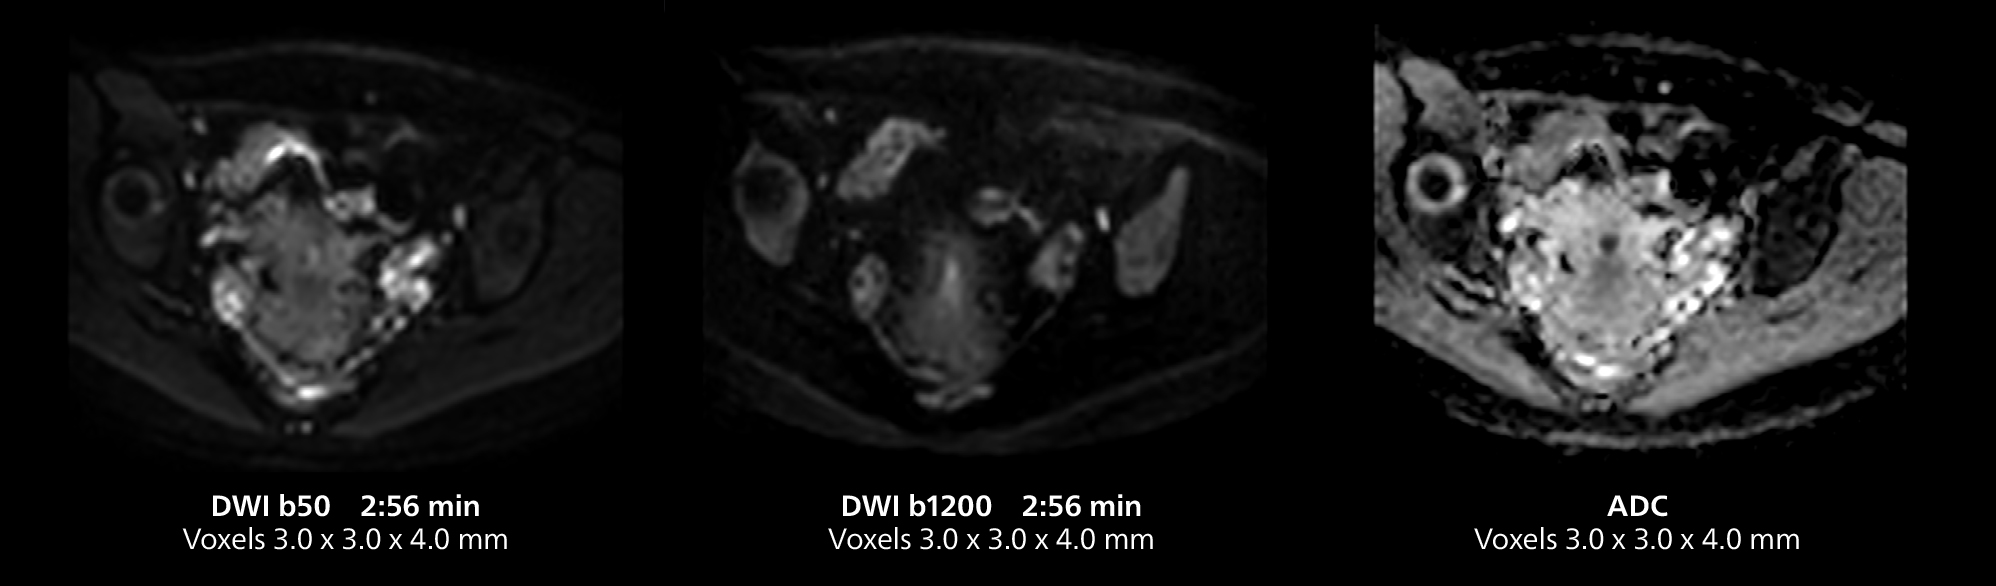

Female pelvis imaging

This MRI case illustrates good resolution and imaging quality obtained within reasonable scan times using the MR 5300 1.5T system with the anterior torso cardiac coil that allows use of a large field of view (FOV).

Free-breathing scans provide reproducibility and patient comfort

Dr. Gellée highlights the robust free-breathing scans as “the feature that makes the biggest difference in my daily work. The 3D free breathing sequences are very reproducible, and the axial acquisition is very good. For example, in endometriosis, which is one of my focus areas, it provides high contrast and good resolution so that I can see small details. We also use free breathing for liver and pancreas imaging. In multi-phase liver studies, 4D Free Breathing delivers 3-second temporal resolution, making a dynamic scan with more than one arterial phase possible.”